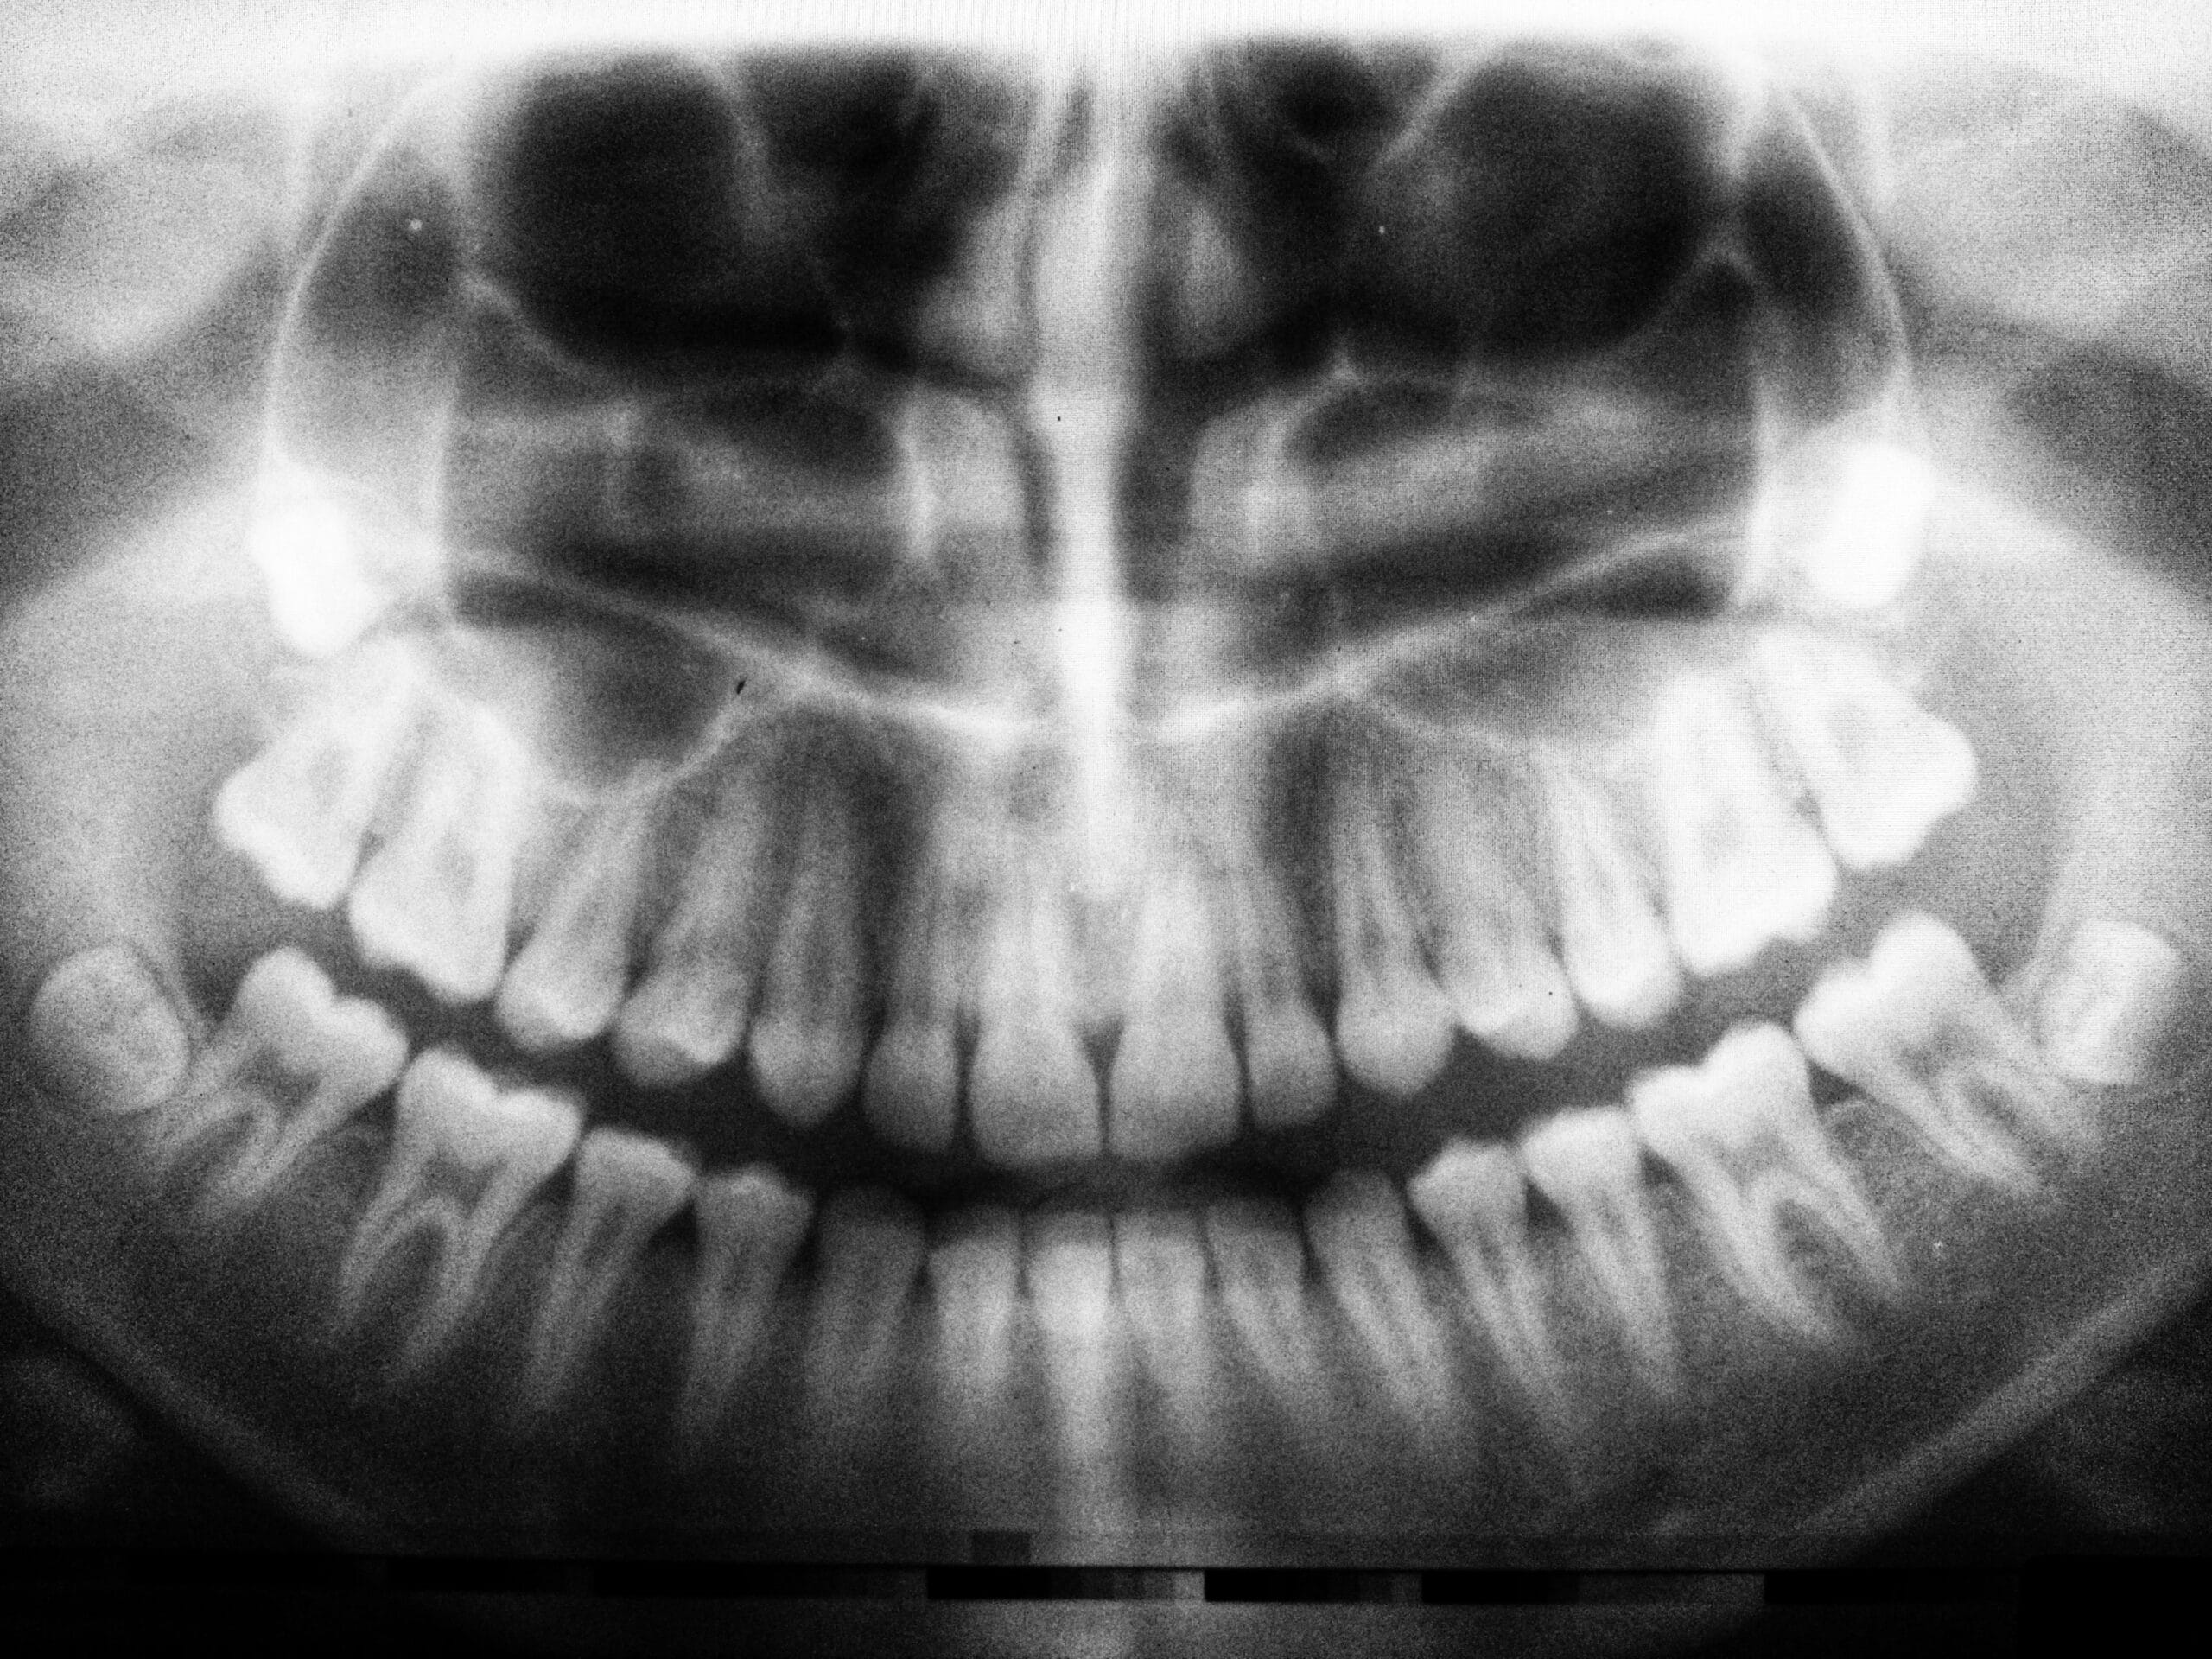

Panoramic X-Rays

Our panoramic x-ray machine is digital and allows us to check the health and position of your teeth. It also allows the dentists to see the bones of your jaw to check for disease, monitor growth or locate wisdom teeth. Our dentists recommend that you have one taken every 5-7 years to monitor your overall oral health. We routinely take them once a child is about 8 years old to see if they are developing normally and if all of their adult teeth are developing. This allows us to intervene if necessary to help correct abnormalities. Panoramic x-rays are taken before orthodontic treatment (braces) is started to plan the course of treatment. We also take them before wisdom teeth are extracted to locate the wisdom teeth as well as the location of the nerves and sinuses to assess the risks of the procedure. Routinely taking a panoramic x-ray helps our dentists detect problems while they are hopefully small – from impacted wisdom teeth to missing adult teeth, from cysts growing in your jaw bone to oral cancers. These panoramic x-rays give the dentist and you a great overall view of your mouth. Check out our blog post about panoramic x-rays for more information.